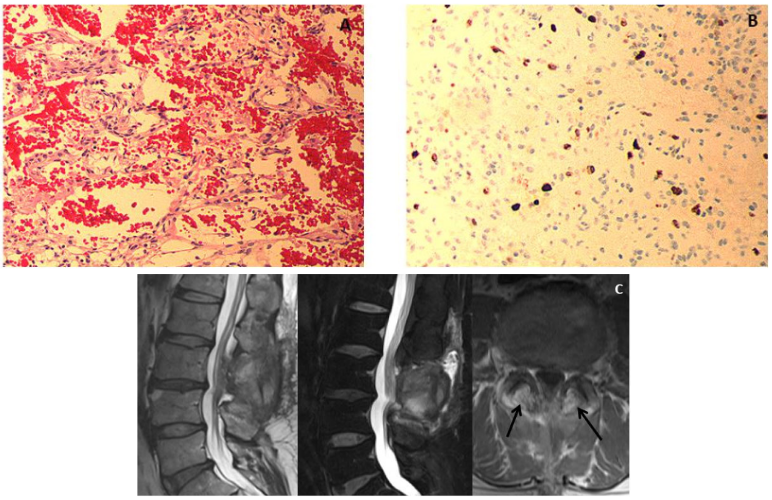

The lesion consisted of blood vessels and mesenchymal spindle-shaped cells intermingled with the vessels. These vessels had thin-walled lobular architecture with variable caliber. The vessels were poorly circumscribed and arranged irregularly (Figure 4A). No evidence of macrophages suggestive of inflammation was found. Immunohistological staining showed the endothelial cells were positive for CD31, CD34, and vimentin, but negative for epithelial membrane antigen and somatostatin receptor 2A. The MIB-1 index was approximately 2-3% (Figure 4B). These histopathological findings were consistent with SECH.

Postoperatively, he had an eventful course. His low back pain and urinary incontinence gradually improved, but numbness remained. MRI at 2 months postoperatively showed that the epidural lesion had completely disappeared, but abnormal intraosseous signals in the bilateral pedicles were seen, suggestive of tumor remnant (Figure 4C). He has continued follow up as an outpatient.

Figure 4 Histopathological findings. (A) Hematoxylin and eosin staining showed numerous capillary vessels of varying sizes intermingled with spindle-shaped lobular cells (×100). (B) MIB-1 index was not so high, approximately 2-3% (×100). These findings were compatible with capillary hemangioma. (C) Postoperative magnetic resonance images. The epidural mass lesion was completely resected, but abnormal intensity signals were apparent in the bilateral pedicles (black arrows), suggestive of remnant tumor.